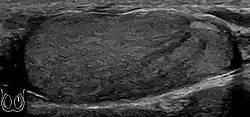

Primary leukemia of the testis is rare. However, due to the presence of blood-testis barrier, chemotherapeutic agents are unable to reach the testis, hence in boys with acute lymphoblastic leukemia, testicular involvement is reported in 5% to 10% of patients, with the majority found during clinical remission. The sonographic appearance of leukemia of the testis can be quite varied, as the tumors may be unilateral or bilateral, diffuse or focal, hypoechoic or hyperechoic. These findings are usually indistinguishable from that of the lymphoma [Fig. 9].

Fig. 9. Leukemia. Diffuse hypoechoic infiltrative lesions are seen involving the whole testis, indistinguishable from that of the lymphoma.